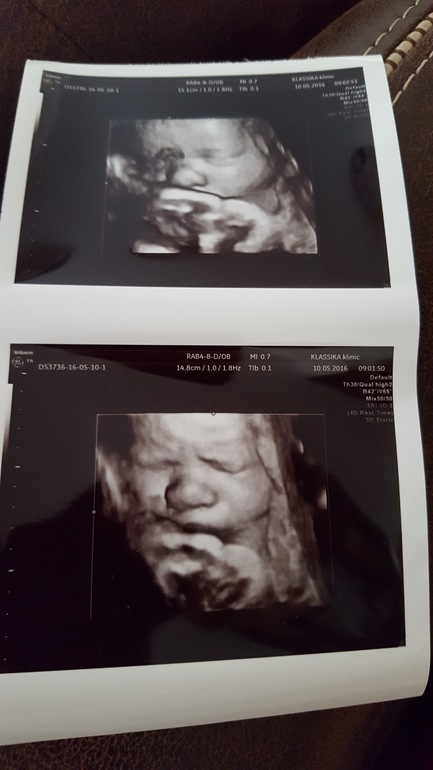

Сегодня делала финальное УЗИ. Доктор начал с поиска удачного кадра для 3D фото. Сначала на лице была пуповина, но все же он смог перевернуть фото так, чтобы увидеть все личико полностью. А там такое чудо чудесное, курносенькое и смешное)))

Зайчик мой любимый, сыночек, спал и потом стал закрываться ручкой)))

Потом посмотрел все, о чем я просила. Что имеем на сегодняшний день: весим мы 3202 гр., обвития нет, лежим в головном. Количество вод нормальное. Доплер сосудов в норме. Плацента 2 степени зрелости и поднялась до 63 мм от зева!!!!, что меня очень обрадовало. Зев сомкнут и шейка до 32 мм. ВСЕ У НАС ХОРОШО!!!! Срок по УЗИ - 37,3 недельки.

В конце сделал нам 2 фотографии, чтобы можно было любоваться до появления малыша!

И вот фото моей сладости сладкой